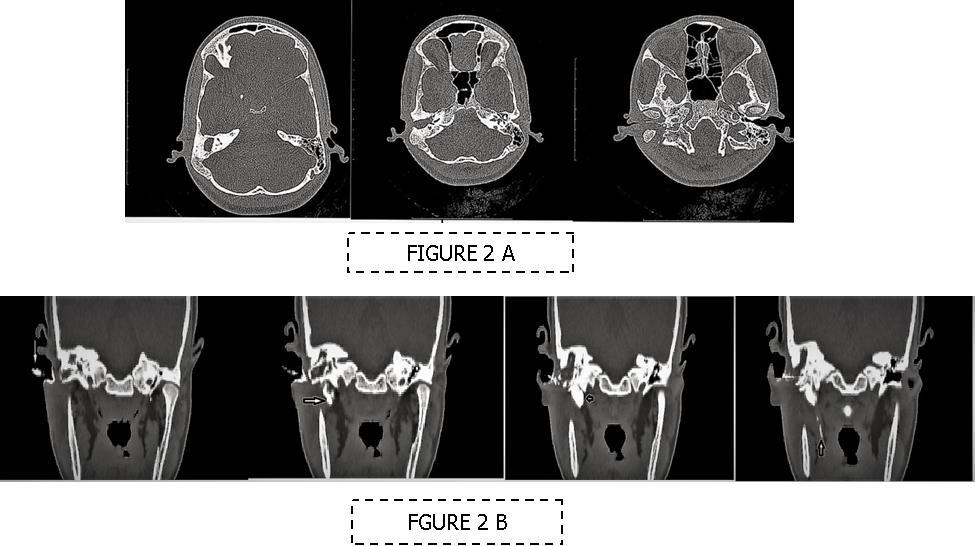

A 13 year old girl presented in ENT outpatient department with complains of recurrent right ear purulent discharge from pre and post auricular area for last 5 years. She had a history of incision and drainage in right post auricular area six months prior for similar complain. On local examination, there was right Grade II8microtia with atretic External Auditory Canal (EAC) and pre-auricular skin tag (Figure 1). A small fistulous opening was also seen in right cavum conchae region. Left ear examination was normal with intact tympanic membrane. Tuning fork tests using 256 and 512 Hz tuning forks showed moderate to severe conductive hearing loss in right ear with Rinne’s test positive in left ear. HRCT scan of temporal bones showed membranous atresia of right EAC with grade II microtia. Soft tissue density was seen filling the EAC and the entire middle ear cavity (Figure 2A). A CT based fistulogram done four months before our consultation identified multiple fistulous tracts situated in post auricular region and anterior to stylomastoid foramen in inframastoid region. These fistulous tracts were communicating through middle ear cavity (Figure 2B). There was associated erosion of posteroinferior and anteroinferior wall of EAC. Ossicles were dysplastic or eroded. Inner ear structures were normal. Patient underwent right radical mastoidectomy with wide conchal meatoplasty under general anaesthesia. Intraoperatively, there was right EAC membranous atresia with fistulous opening in cavum conchae. Cholesteatoma sac was seen filling the mastoid antrum area extending into middle ear cavity and EAC with erosion of posterior canal wall. Except remnant of malleus head which was fixed to epitympanic wall, no other ossicle was found. Oval window area showed bony depression without any overlying stapes footplate (Figure 3). Lateral semicircular canal bulge, facial nerve canal and chorda tympani were found at their usual locations (Figure 4). Obliteration of mastoid cavity posterior to vertical segment of bony facial canal was done using pedicled temporalis muscle flap to reduce the size of postoperative cavity. Middle ear cavity was covered with temporalis fascia graft.

Figure 2.(A-B) HRCT imaging. (A) Right canal atresia with soft tissue density behind it (B) CT sino-gram showing multiple (arrow marked) sinuses communicating to right middle ear cavity.